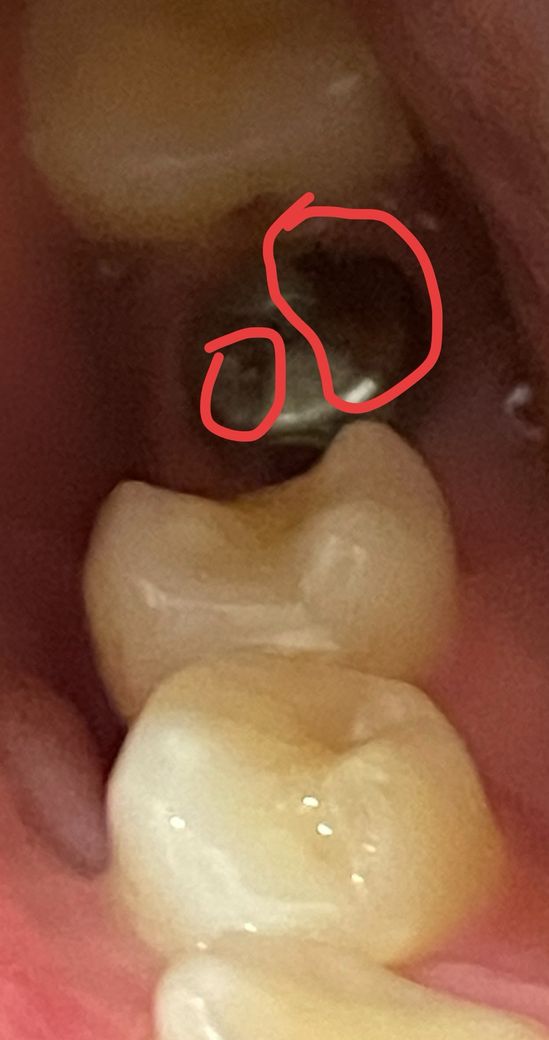

힐링어버먼트 까매짐ㅠㅠ 괜찮을까요..?

대학병원에서 네오로 했고 오늘이 거의 10일차?인데 위에가 까매졌어요.. 뚜겅 부분? 군데군데가 까맣네요 문제 없을까요? 다음 예약이 한달뒤라 걱정이 되네요

분명 피딱지 붙어있는 것 같았는데.. 까매져서 양치를 해도 그대로네요….

티타늄? 소재라 산화된거라는데 맞는건지

1. 힐링 어버트먼트는 잇몸 모양 형성을 위한 임시 뚜껑일 뿐 계속 쓰는 거 아니기 때문에 별 상관없습니다.

2. 사진상으론 잘 안보이는데, 힐링 어벗 제원이 써진 잉크색이 아닐까도 싶네요. 아래 링크에서 사진 참고하시고요.

3. 녹슬거나 하는 재료는 아닙니다.

힐링 어버트 먼트는 잇몸이 아무는데 사용되는것이기 대문에 색상이 변경되었다고 해도 문제가 되지는 않습니다 너무 걱정하지 않아도 될것으로 생각됩니다